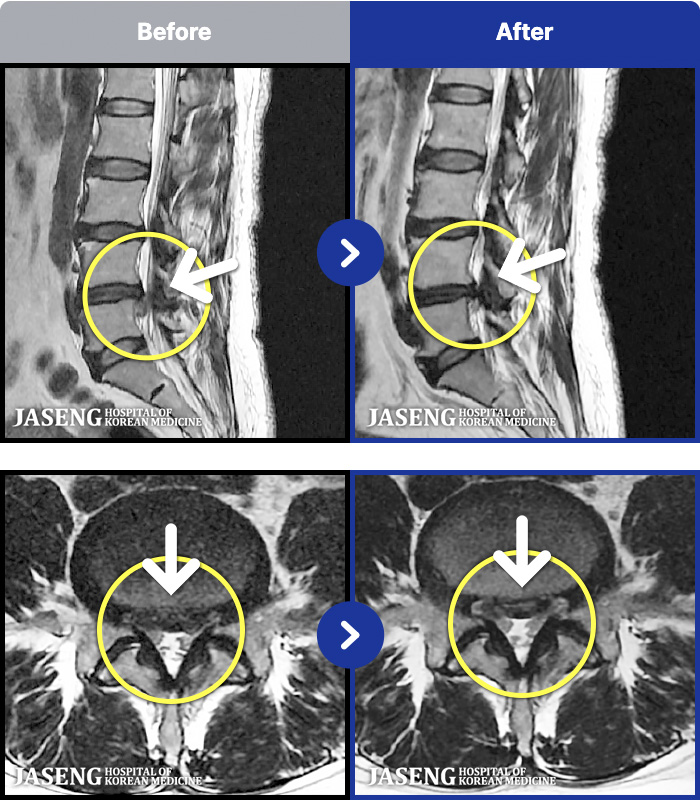

MRI ġ

1,240 MRI ũ ʸ Ȯϼ.

㸮 ϻ .